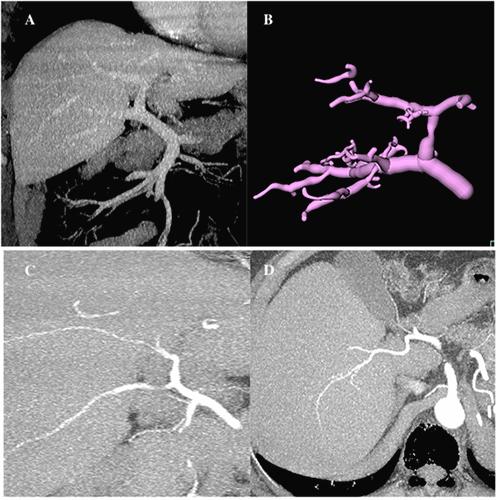

Figure 1. Preoperative Recipient CT Scan. Published with Permission

Large, space-occupying tumor causing compression of the vena cava and a significant right-sided pleural effusion

The recipient, a woman in her 40s (56.2 kg), presented with a large, biopsy-proven, well-differentiated metastatic neuroendocrine tumor confined to the liver (origin uncertain). Vena cava compression from the tumor (affecting approximately 85% of the liver) led to abdominal distention, dyspnea, and lower extremity edema (Figure 1). Despite eight months of disease control with monthly octreotide injections, progressive decline in quality of life prompted consideration for liver transplantation (LT). Preoperative workup included an octreotide scan showing no extrahepatic lesions, a stable chromogranin A level of 31 ng/mL, and a Model for End-Stage Liver Disease (MELD) score of 10.